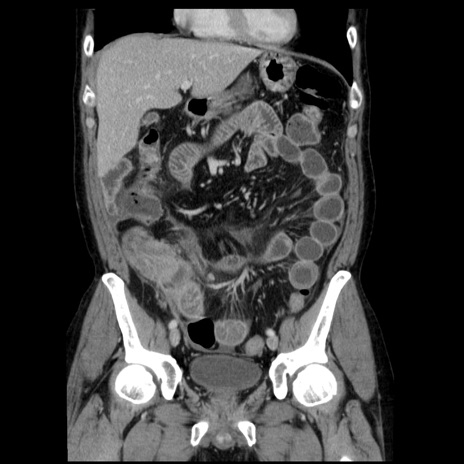

症例29(冠状断像)

【症例】40歳代男性

【現病歴】2日前から胃痛あり。徐々に周期的な激痛に変化した。本日になっても激痛があるため受診。

【身体所見】意識清明、BT 38-39℃台あり、腹部:膨満、やや硬、右下腹部に圧痛あり。

【データ】WBC 8500、CRP 23.26